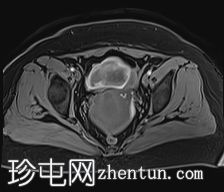

轴位

STIR序列

可见子宫外腹腔内妊娠囊,内含胎儿组织。

该妊娠囊向后推移子宫,并与剖宫产瘢痕凹陷处紧密相连。

该妊娠囊与相关肠袢无法分离。可见其与性腺血管密不可分,且性腺血管明显突出。

沿妊娠囊下缘可见一处异质性局灶性积液,最大轴向尺寸约为 8.4 × 5.5 cm,T1 加权像呈异质性高信号,T2 加权像呈异质性中等信号,T1 脂肪抑制序列未见信号下降,提示为血液成分。该积液压迫膀胱。

左侧卵巢无法辨认。

右侧卵巢未见实性或囊性肿块。

子宫体积增大,后倾,子宫内膜厚度约 1 cm,子宫下段前壁可见局灶性变薄(既往子宫瘢痕)。子宫连接区完整,未见肌层肿块。可见子宫内膜腔边缘有血性分泌物。